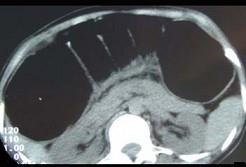

问题 女,30岁,便秘、腹痛腹胀多年,CT检查如图,最可能的诊断是 ( )

选项 A、结肠肠扭转 B、结肠肠栓塞 C、先天性巨结肠 D、结肠肠套叠 E、结肠肠梗阻

答案 C